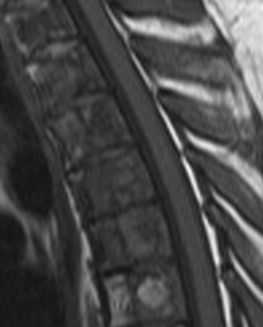

(Слева) Сагиттальный срез, FS Т2-ВИ, пациент после курса лучевой терапии по поводу рака полости рта: патологическое веретеновидное утолщение и гиперинтенсивность сигнала шейного отдела спинного мозга на уровне С2-СЗ. Обратите также внимание на диффузное подавление сигнала костного мозга тел позвонков вследствие его постлучевой жировой перестройки.

(Справа) Сагиттальный срез, FS T1-ВИ с КУ, пациент после курса лучевой терапии по поводу рака полости рта: в толще спинного мозга на уровне С2 определяется очаг накопления контраста. Обратите внимание на диффузное подавление сигнала костного мозга тел позвонков вследствие его постлучевой жировой перестройки.